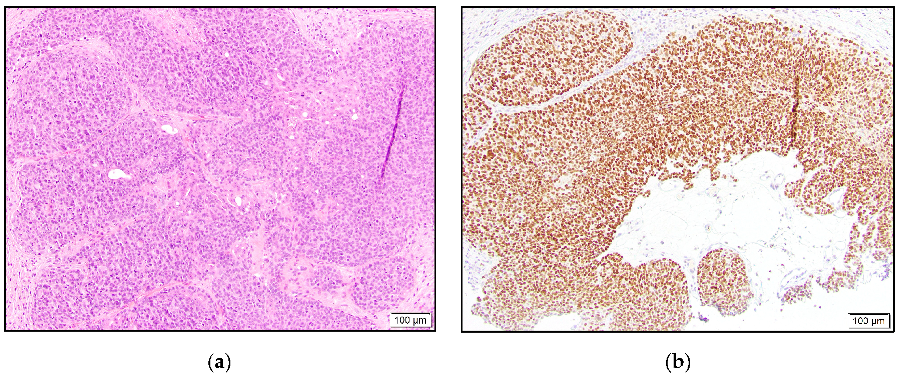

Of the two syringoid eccrine carcinomas, one was intermediate positive, and the other case was negative. Three of our hidradenocarcinomas were high positive (Figure 2), and one case was negative for TRPS1 staining.

Figure 2.

Hidradenocarcinoma with dermal tumor nodule composed of eosinophilic cells and mitoses (a) and high positive TRPS1 expression (b).